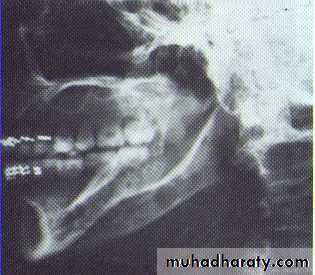

•Large multilocular aneurysmal bone cyst

in the ramus with marked expansion and

the displacement of/8.